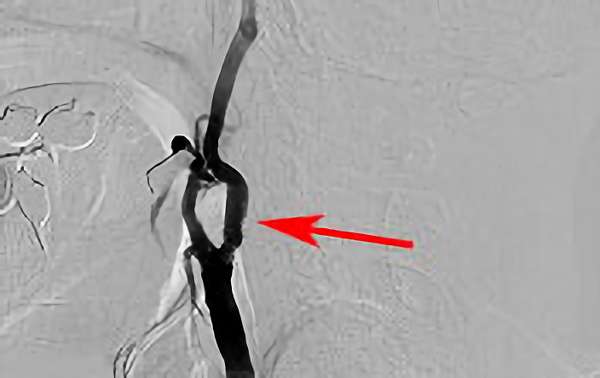

'18年10月17日

左内頚動脈狭窄症

70代

院内外来

手術写真

治療

前

中

後